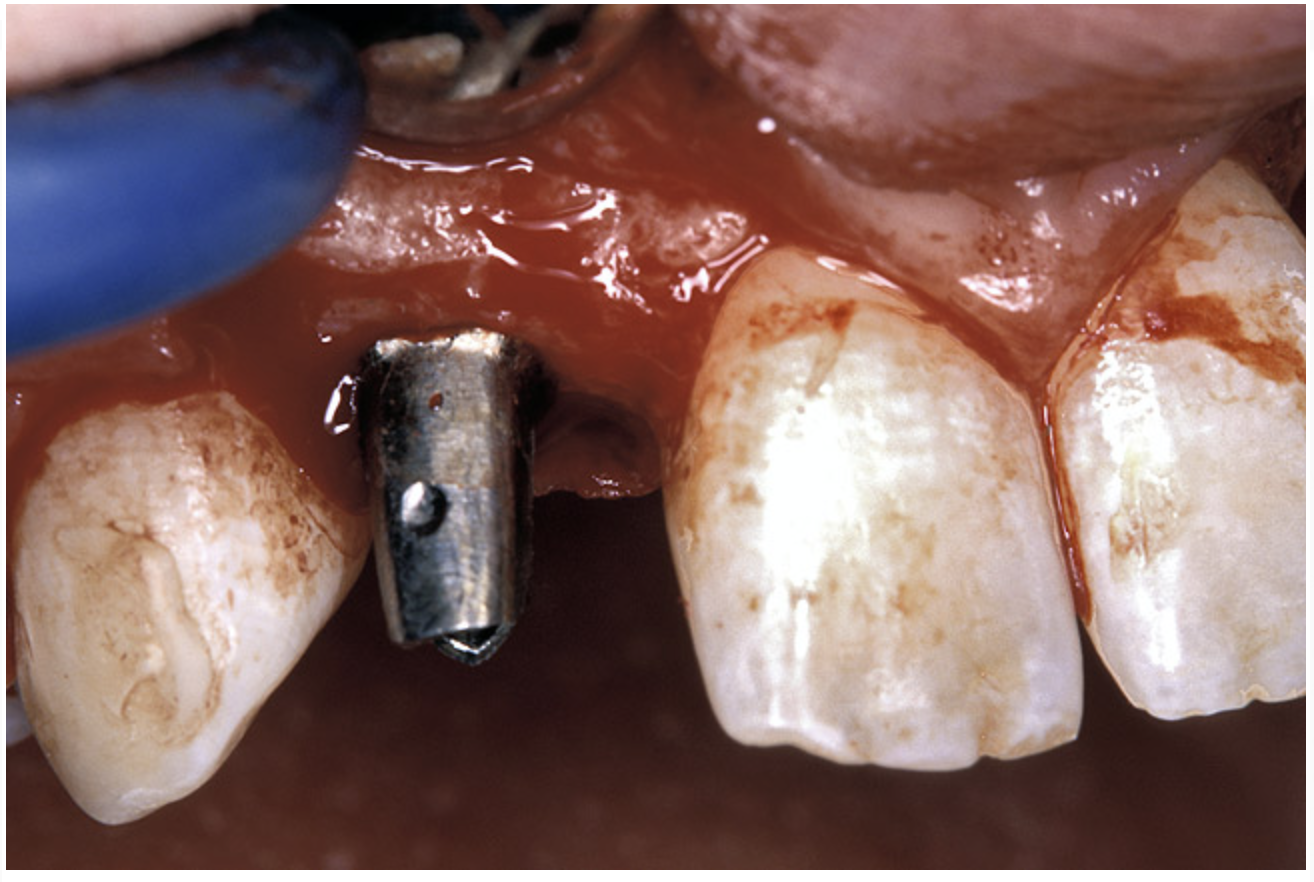

The 3.7-mm diameter Tapered Screw-Vent implant drilling sequence required three drills: pilot, intermediate, and final sizing. Thus, three separate templates were fabricated to accommodate these sizes. The templates were removed easily and replaced with the next sequential size in less time than it takes to change the drill on the surgical handpiece. After the osteotomies had been completed, the implants were delivered to the site (Figure 16A and Figure 16B). For this internal hex connection implant, the author r.commends that the flat of the antirotational hex be positioned to the facial for proper orientation of the restorative components (Figure 17A). Preprepared margins were created from a milled titanium fixture mount transfer post, which was delivered to the implant as support for an immediate transitional restoration. The facial “dot” helped confirm the orientation of the abutment to the facially positioned flat side of the internal hex connection (Figure 17B). Before cementation of the transitional acrylic restorations, a closed-tray, fixture-level impression was made, and a soft-tissue model fabricated.

Figure 16a  After (A) the osteotomies were completed, (B) the implants were placed.

Figure 16a

Figure 16b  After (A) the osteotomies were completed, (B) the implants were placed.

Figure 16b

Figure 17a  By predetermining the necessary orientation of the restorative components, the implant’s antirotational hex was positioned correctly.

Figure 17a

Figure 17b  By predetermining the necessary orientation of the restorative components, the implant’s antirotational hex was positioned correctly.

Figure 17b